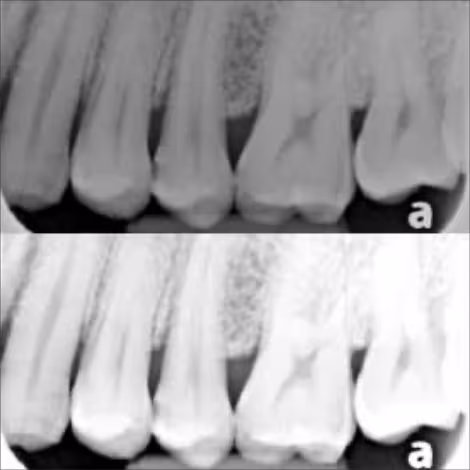

This course explains the principle of image formation on any x-ray receptor, starting from the interaction between the x-ray and the radiographed object. This course will also explain the image quality factors such as the kVp, mAs, spatial resolution, contrast resolution, and image sharpness.